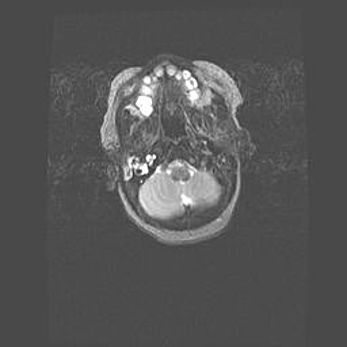

Подострая гематома правой гемисферы мозжечка.

Наружная гидроцефалия.

Возраст: 15 дней

Вес: 3100 г

Пол: женский

Окружность головы: 37 см

Срок гестации: 35-36 недель

При открытой наружной форме гидроцефалии у новорожденных расширяются и переполняются субарахноидные пространства.

Кровоизлияния в мозжечок имеют две клинико-анатомические формы: полушарные гематомы и кровоизлияния в червь.

К появлению этой патологии может привести: повреждения головного мозга, возникающие в результате асфиксии и гипоксии плода при беременности, или травмы во время родов. Редко гематома мозжечка может быть результатом первичной коагулопатии и сосудистой мальформации, диссеминированном внутрисосудистом свертывании, изоиммунной тромбоцитопении.